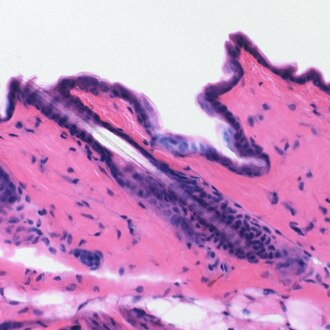

Hematein je prirodno bojilo, C16H1206 (C.I. 75290), tvori crvene iglice koje se raspadaju na temperaturi višoj od 200 °C. Malo je topljiv u etanolu i eteru (žuta boja), te u vodi (crvena boja). Dobro je topljiv u alkalijama (modroljubičasta boja) i mineralnim kiselinama (crvena boja). Hematein čini sa solima teških metala složene spojeve, i to od modroljubičastih s bakrenim i kositrenim solima do crnih sa željeznim solima. Hematein nastaje oksidacijom hematoksilina koji se nalazi u plavom drvetu kampečevini (lat. Lignum campechianum, L. haematoxyli). Upotrebljava se za bojenje i tiskanje pamuka, svile, poliamida, vune, krzna i kože. Dobiva se vrlo postojana plavocrna boja, te kao pigment za izradu crne tinte, tiskarskih i slikarskih uljenih boja. Hematoksilinski preparati mogu se upotrebljavati kao antioksidacijska sredstva za nezasićene masne kiseline, kao reagens za dokazivanje truljenja hrane, te za bojenje histoloških preparata.